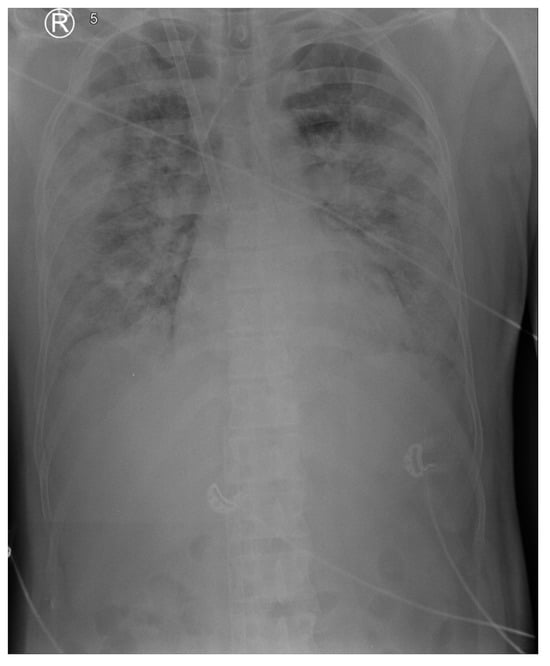

Over the 3 h following admission, the patient’s oxygenation worsened. After a short period in the supine position due to the insertion of a left subclavian central vein catheter (CVC), the patient was placed in a prone position again, with minimal benefit. The recruitment maneuver (BILEVEL: PEEP High 40 cm H2O, PEEP Low 20 cm H2O, I:E = 5:1 for 1 min) yielded no lung recruitment or improvement in oxygenation. As the hypoxemia persisted with a PaO2/FiO2 ratio below 80 despite optimized ventilation with optimal individual PEEP determined (decremental PEEP staircase titration according to the best compliance), cisatracurium infusion and prone positioning, VV ECMO support was instituted (ECLS day 1/MV day 2) using a Cardiohelp console with an HLS 7.0 set (both from Maquet, Rastatt, Germany). Using the ultrasound-guided Seldinger technique, a drainage cannula was inserted into the right femoral vein (venous, French 23, 55 cm) and a return cannula into the right jugular vein (arterial, French 19, 15 cm). A follow-up chest radiograph and bedside ultrasound were performed to confirm the cannula positioning (Figure 1).

Figure 1.

Chest X-ray on ECLS day 1. Chest X-ray revealed massive, confluent, bilateral opacities.